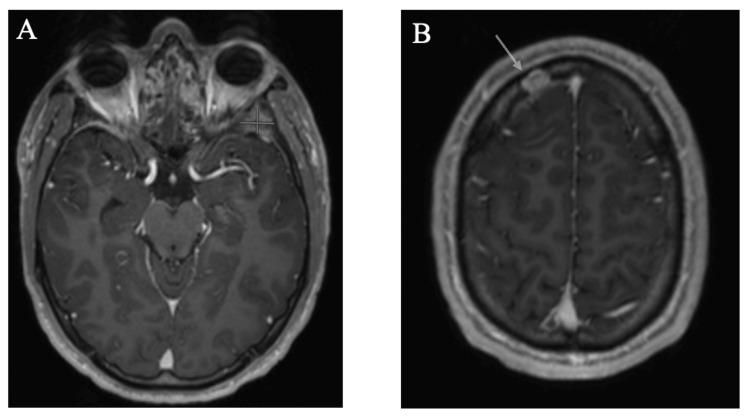

Langerhans cell histiocytosis (LCH) is a proliferative disorder causing normally immune-responsive Langerhans cells to abnormally accumulate in various tissues and organs. Most available data on LCH is derived from pediatric populations, with limited literature focusing on adult LCH, which is rarer. Multisystem involvement in LCH, including central nervous system (CNS) involvement, is often higher risk and poorer prognosis. Standardized treatment recommendations remain limited, particularly in adolescent and young adult (AYA) populations. Discussed below is a case of AYA-onset multisystem LCH with CNS and skeletal system involvement, which was successfully treated with cladribine therapy. An 18-year-old male with no significant past medical history presented with left orbital pain and swelling. Laboratory, imaging, and biopsy results were consistent with a diagnosis of multisystem LCH. The patient was started on cladribine at 0.1 mg/kg/day for 7 days, along with Pneumocystis pneumonia prophylaxis and symptomatic management of facial pain and headaches. After four cycles of cladribine therapy, the patient exhibited symptomatic resolution and complete response of CNS and skeletal lesions. This highlights one potential therapeutic approach yielding a favorable outcome in a borderline case of AYA-onset LCH without targetable mutations on tissue next-generation sequencing (NGS). It also underscores the need for systemic therapy in patients with CNS involvement to avoid future long-term neurodegenerative complications. Further prospective studies and clinical trials are warranted to yield standardized treatment regimens for adult patients with LCH, particularly with multisystem involvement, including CNS.

朗格汉斯细胞组织细胞增多症(LCH)是一种增殖性疾病,可导致正常具有免疫反应性的朗格汉斯细胞在各种组织和器官中异常积聚。关于LCH的现有数据大多来自儿科人群,针对成人LCH的文献有限,而成人LCH更为罕见。LCH的多系统受累,包括中枢神经系统(CNS)受累,往往风险更高且预后更差。标准化治疗建议仍然有限,尤其是在青少年和青年(AYA)人群中。以下讨论的是一例AYA起病的多系统LCH,伴有CNS和骨骼系统受累,该病例通过克拉屈滨治疗成功治愈。一名既往无重大病史的18岁男性出现左眼眶疼痛和肿胀。实验室、影像学和活检结果均符合多系统LCH的诊断。患者开始接受克拉屈滨治疗,剂量为0.1mg/kg/天,持续7天,同时进行肺孢子菌肺炎预防以及面部疼痛和头痛的对症治疗。经过四个周期的克拉屈滨治疗后,患者症状缓解,CNS和骨骼病变完全缓解。这突出了一种潜在的治疗方法,在一例AYA起病的LCH临界病例中取得了良好的治疗效果,该病例在组织下一代测序(NGS)上没有可靶向的突变。这也强调了对于CNS受累患者进行全身治疗以避免未来长期神经退行性并发症的必要性。有必要进行进一步的前瞻性研究和临床试验,以制定针对成人LCH患者,尤其是伴有多系统受累(包括CNS受累)的标准化治疗方案。